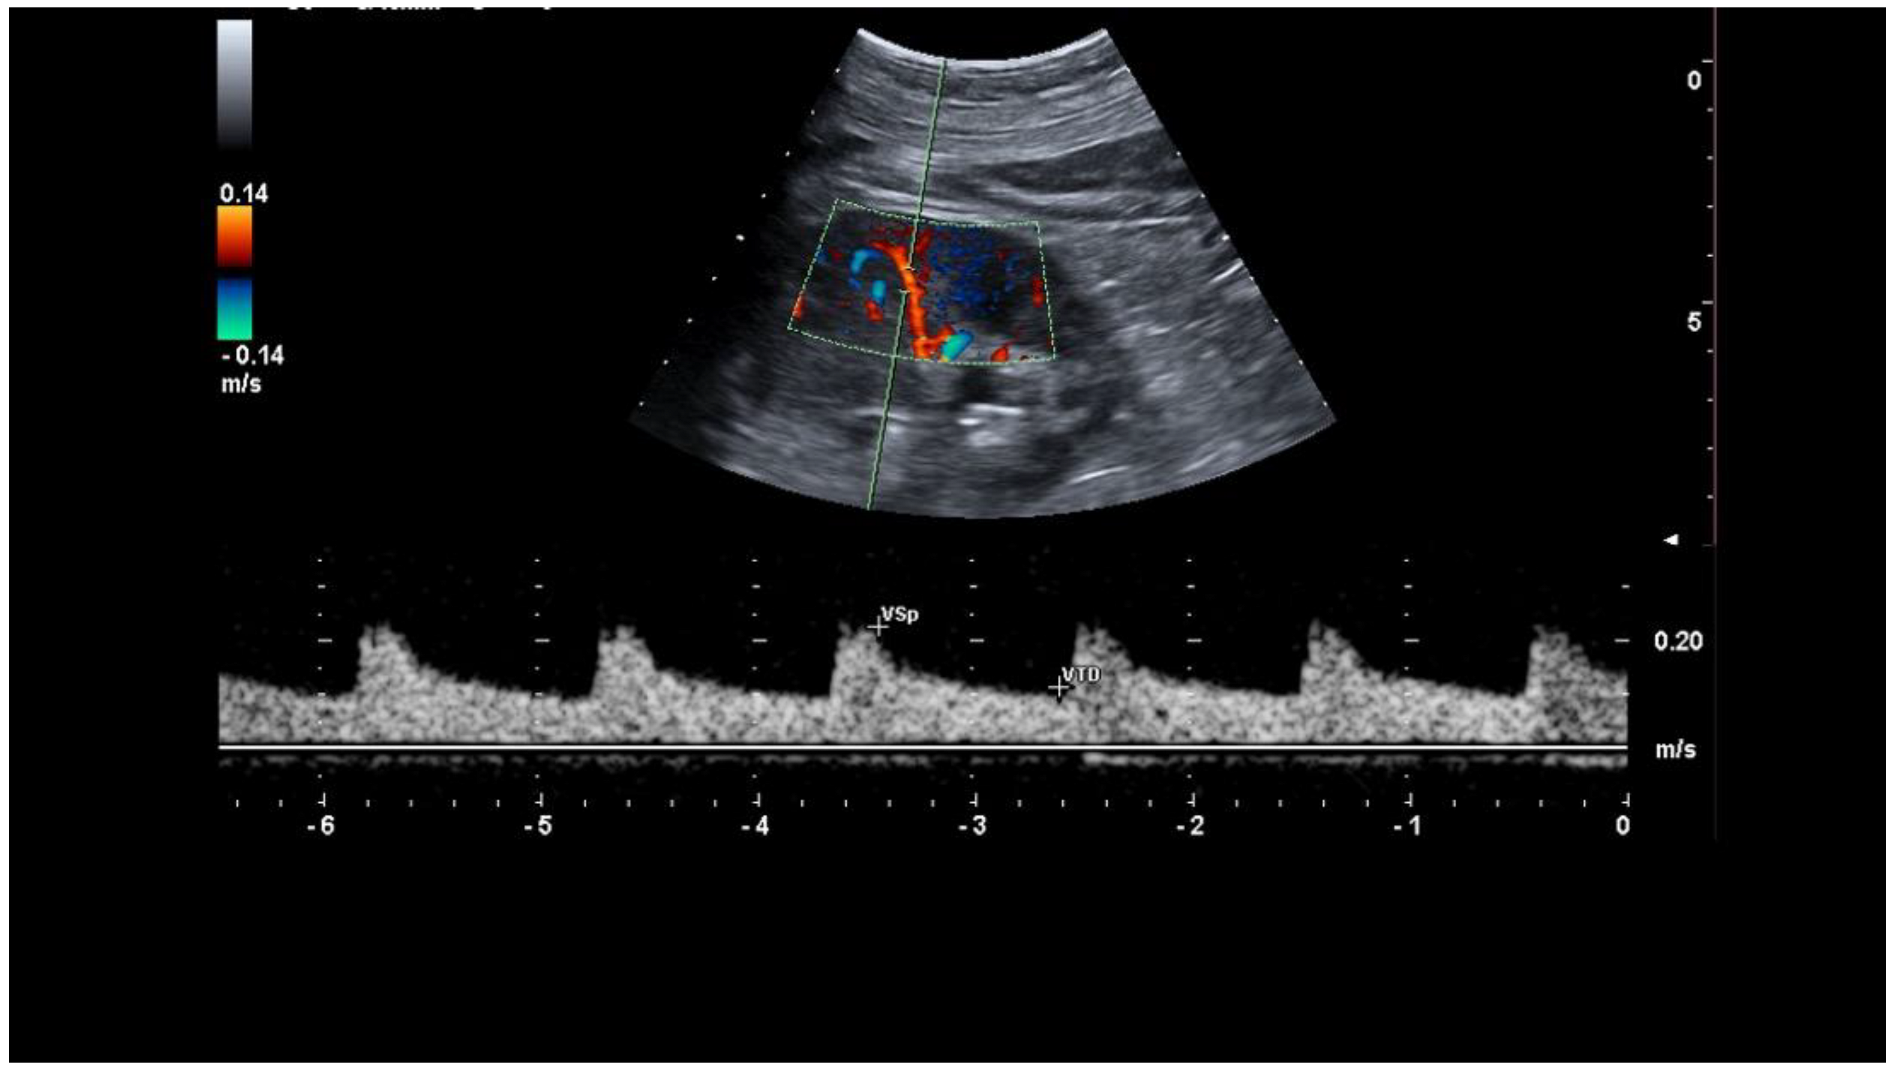

2.2. Baseline RRI Measurement

- Samoni, S.; Nalesso, F.; Meola, M.; Villa, G.; De Cal, M.; De Rosa, S.; Petrucci, I.; Brendolan, A.; Rosner, M.H.; Ronco, C. Intra-Parenchymal Renal Resistive Index Variation (IRRIV) Describes Renal Functional Reserve (RFR): Pilot Study in Healthy Volunteers. Front. Physiol. 2016, 7, 286. [Google Scholar] [CrossRef]

- Samoni, S.; Villa, G.; De Rosa, S.; Husain-Syed, F.; Guglielmetti, G.; Tofani, L.; De Cal, M.; Nalesso, F.; Meola, M.; Ronco, C. Ultrasonographic Intraparenchymal Renal Resistive Index Variation for Assessing Renal Functional Reserve in Patients Scheduled for Cardiac Surgery: A Pilot Study. Blood Purif. 2022, 51, 147–154. [Google Scholar] [CrossRef]

- Tublin, M.E.; Bude, R.O.; Platt, J.F. Review. The resistive index in renal Doppler sonography: Where do we stand? AJR Am. J. Roentgenol. 2003, 180, 885–892. [Google Scholar] [CrossRef]